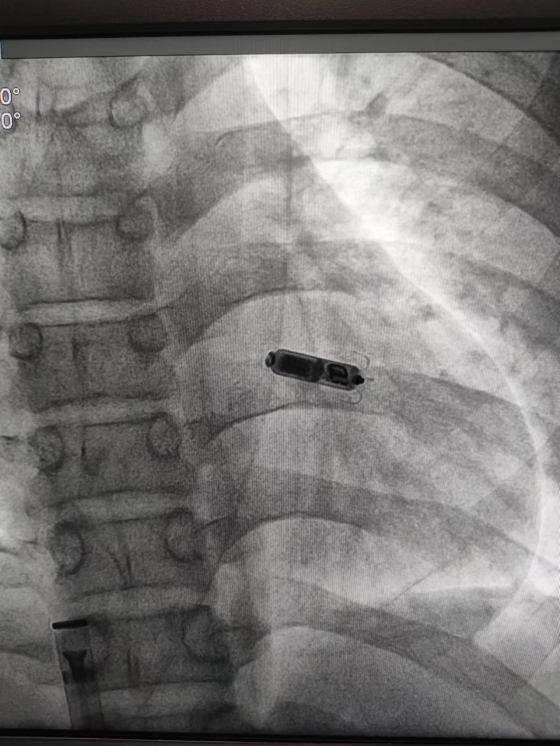

起搏器植入术后

7月13日,患者在局麻下接受了无导线永久起搏器植入术,手术过程顺利,共历时40分钟,患者手术中无需切开缝合,微创方式即可植入起搏器,术后恢复良好,复查心电图起搏器工作良好。一周内安全出院。